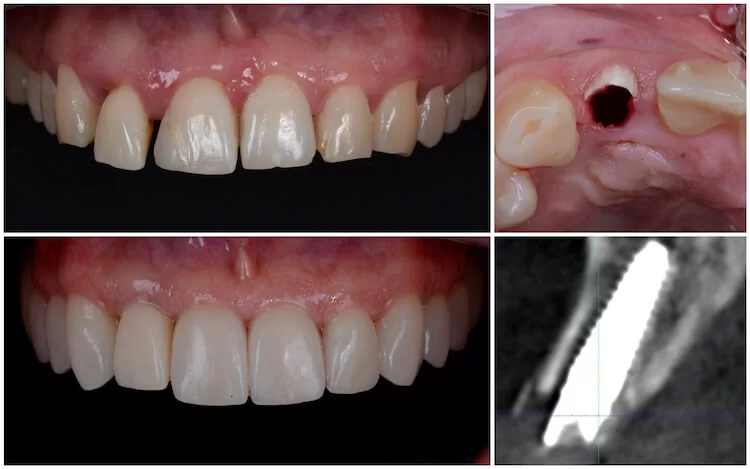

A fogimplantátum beültetés során egy speciális, biokompatibilis titán implantátum kerül az állcsontba, amely a hiányzó fog gyökerét helyettesíti. Erre kerül később a végleges fogpótlás – korona, híd vagy akár teljes fogsor.

A cél nem csupán a fog pótlása, hanem a rágási stabilitás és az állcsont terhelésének helyreállítása.

- Digitális diagnosztika (szükség esetén 3D képalkotás)

- Fogimplantátum beültetés érzéstelenítésben

A kezelés során kiemelten fontos a precíz tervezés, amely jelentősen csökkenti a kellemetlenséget és a kockázatot.